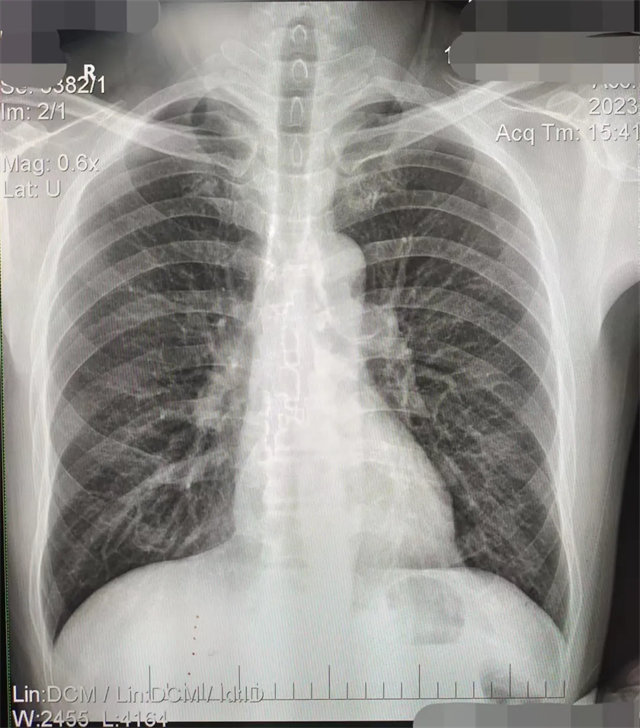

缺陷:雙側(cè)胸鎖關(guān)節(jié)不對(duì)稱(chēng),且有手機(jī)顯影。

解決:去除手機(jī)后,使患者左側(cè)緊貼成像件曝光。